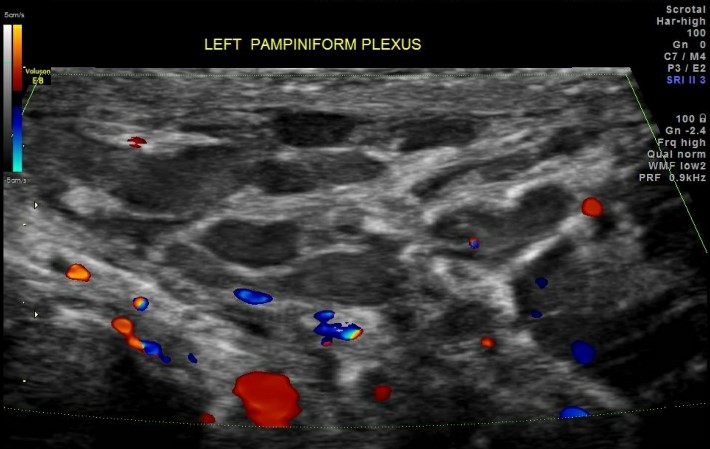

- Độ 1: là tình trạng giãn tĩnh mạch thừng tinh tìm ẩn, người bệnh thường đi khám vì tình trạng đau âm ỉ ở tinh hoàn, lan lên bẹn và vùng lưng cùng bên. Những trường hợp này chỉ được phát hiện bởi những bác sĩ chuyên ngành Nam học có nhiều kinh nghiệm, siêu âm có thể phát hiện khoảng 70% các trường hợp.